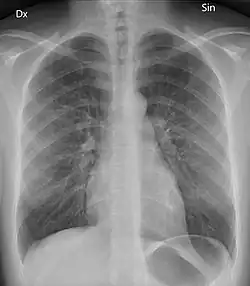

Chest

_chest_radiograph_(X-ray).jpg)

Chest radiographs are used to diagnose many conditions involving the chest wall, including its bones, and also structures contained within the thoracic cavity including the lungs, heart, and great vessels. Conditions commonly identified by chest radiography include pneumonia, pneumothorax, interstitial lung disease, heart failure, bone fracture and hiatal hernia. Typically an erect postero-anterior (PA) projection is the preferred projection. Chest radiographs are also used to screen for job-related lung disease in industries such as mining where workers are exposed to dust.[12]

For some conditions of the chest, radiography is good for screening but poor for diagnosis. When a condition is suspected based on chest radiography, additional imaging of the chest can be obtained to definitively diagnose the condition or to provide evidence in favor of the diagnosis suggested by initial chest radiography. Unless a fractured rib is suspected of being displaced, and therefore likely to cause damage to the lungs and other tissue structures, an X-ray of the chest is not necessary as it will not alter patient management.